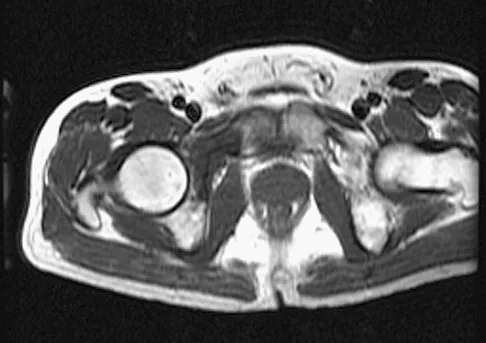

Figures 61a and 61b show the CT and MRI scans of a 40-year-old man who has hip pain. He undergoes total hip arthroplasty and curettage and cementation of the lesion as shown in Figure 61c. Histopathologic photomicrographs of the curettage specimen are shown in Figures 61d and 61e. What is the best course of treatment?

Explanation

The definitive surgery would be removal of the entire resection bed, and in this case of dedifferentiated chondrosarcoma, a hemipelvectomy was performed. The MRI and CT scans show an aggressive cartilage lesion. The histology, representative of a dedifferentiated chondrosarcoma, shows a bimorphic low-grade cartilage lesion with high-grade spindle cell sarcoma. The cartilage lesion is usually an enchondroma or low-grade chondrosarcoma. The dedifferentiated portion is typically a malignant fibrous histocytoma, osteosarcoma, or fibrosarcoma. Weber KL, Pring ME, Sim FH: Treatment and outcome of recurrent pelvic chondrosarcoma. Clin Orthop Relat Res 2002;397:19-28.